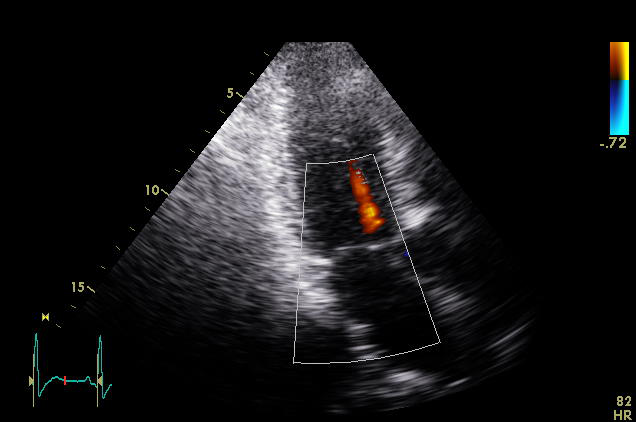

ImageView NameDescription

plax-full-rv-ao plax-full-rv-ao Focus on RV & aorta or colour Doppler over RV/AV/Aorta

plax-tv plax-tv Parasternal inflow view including tricuspid valve

plax-valves-av plax-valves-av PLAX focused on the aortic valve

plax-valves-mv plax-valves-mv PLAX focused on the mitral valve